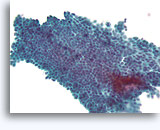

Typische ductale cellen, Borst FNA, Celblok.

Deze naaldspoeling van de patiënt in afbeelding 5 toont benigne ductale cellen als eenlagige epitheelstroken aan de rechterkant van de afbeelding. Aan de linkerkant ziet u een gebied met typische hyperplasie. De stratificatie van de cellen in dit gebied kan niet worden verklaard door tangentieel snijden. Met deze kleine vergroting kunt u de spleetachtige ruimten tussen de stratificerende ductale cellen zien, Ook kenmerkend voor typische ductale hyperplasie is de aanwezigheid van een mengsel van cellen met verschillende cytologische kenmerken (myoepitheliale cellen) in de stratificerende populatie.

Typische ductale cellen, Borst FNA, Celblok.

Deze naaldspoeling van de patiënt in afbeelding 5 toont benigne ductale cellen als eenlagige epitheelstroken aan de rechterkant van de afbeelding. Aan de linkerkant ziet u een gebied met typische hyperplasie. De stratificatie van de cellen in dit gebied kan niet worden verklaard door tangentieel snijden. Met deze kleine vergroting kunt u de spleetachtige ruimten tussen de stratificerende ductale cellen zien, Ook kenmerkend voor typische ductale hyperplasie is de aanwezigheid van een mengsel van cellen met verschillende cytologische kenmerken (myoepitheliale cellen) in de stratificerende populatie.

Typische ductale cellen, Borst FNA, Celblok.

Let op het mengsel van donkerder en lichterkleurende kernen en op de langwerpige ruimten. Bij typische ductale hyperplasie hebben de cellen de neiging om zich langs de as van de ruimten te groeperen (pijlen). Een andere nuttig diagnostisch kenmerk is de uitlijning van de lange as van de kernen van aangrenzende cellen, met een stromings- of vaag patroon van een ‘school vissen’ (open pijl). Deze kenmerken die duidelijk zichtbaar zijn bij een relatie kleine vergroting in histologische coupes, kunnen moeilijk of helemaal niet zichtbaar zijn in cytologische preparaten.

Typische ductale cellen, Borst FNA, Celblok.

Let op het mengsel van donkerder en lichterkleurende kernen en op de langwerpige ruimten. Bij typische ductale hyperplasie hebben de cellen de neiging om zich langs de as van de ruimten te groeperen (pijlen). Een andere nuttig diagnostisch kenmerk is de uitlijning van de lange as van de kernen van aangrenzende cellen, met een stromings- of vaag patroon van een ‘school vissen’ (open pijl). Deze kenmerken die duidelijk zichtbaar zijn bij een relatie kleine vergroting in histologische coupes, kunnen moeilijk of helemaal niet zichtbaar zijn in cytologische preparaten.